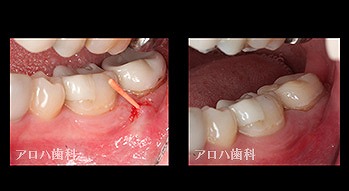

case3

再根管治療

瘻孔の消失

1年予後

case5

左>頬側よりGP挿入。MB根尖の透過像と一致。P根にも透過像。穿孔を疑う。右>術後1年

左>術前

右>術後1年。

頬側の瘻孔